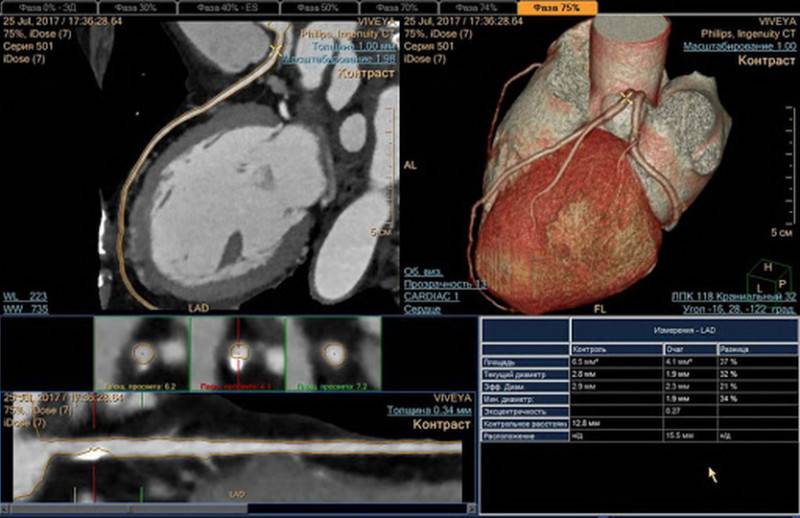

а – обычный снимок грудной клетки, б – компьютерная томография

При одинаковом физическом принципе построения изображений при рентгене и КТ органов грудной клетки различны траектория прохождения рентгеновских лучей через область интереса и техника визуализации. Указанное влияет на информативность изображений.

Компьютерная томография – усовершенствованное рентгеновское исследование. Современные мультиспиральные сканеры способны выполнить несколько десятков снимков в разных проекциях за одну задержку дыхания. Дополнительные программы автоматической корректировки экспозиции помогают уменьшить лучевую нагрузку в 1,5-2 раза. При необходимости доступны мультипланарные реконструкции изучаемой зоны, оценка сосудов с использованием ангиорежимов, изучение патологии с любого ракурса.